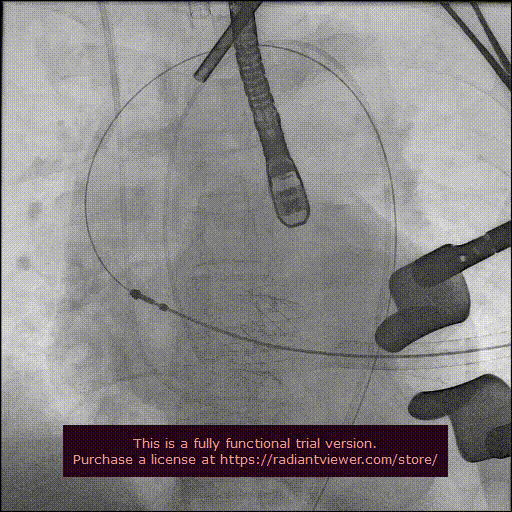

造影显示主动脉窦部

从心尖置入输送系统

定位件入窦

瓣膜降至瓣环平面

释放瓣膜

造影确认瓣膜位置

撤出输送系统

造影确认植入效果